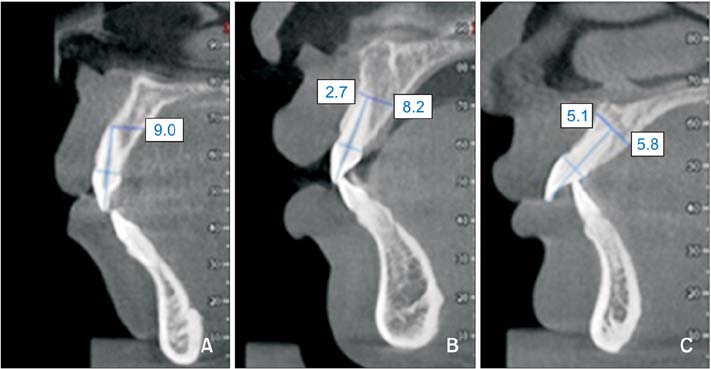

아래 그림을 보시면 보다 쉽게 이해하실 수 있을 겁니다.